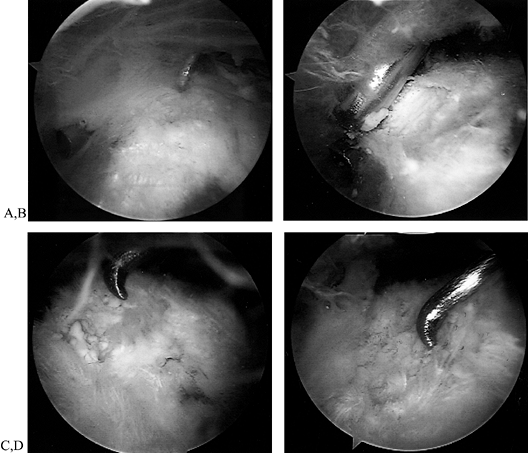

Visualize an area of increased vascularity on the bursal surface of the tendon (Fig. 79.20A; see also COLOR FIG. 79.20). Insert a probe or needle from the lateral portal to confirm the deposit by palpation. Uncover the deposit using a shaver (Fig. 79.20B). Note the chalklike flakes and nuggets (Fig. 79.20C). Continue debridement until the base is clean of calcium particles (Fig. 79.20D). A curet can be helpful in scraping out all remaining particles.

Figure 79.20. (See COLOR FIGURE 79.20) Calcific tendinitis. A: Note inflamed area on bursal surface of the supraspinatus, which corresponds to an underlying calcific deposit. B: Unroofing of the calcific deposit by gentle shaving. C: Full extent of the deposit. D: After complete debridement, the tendon remains intact. -